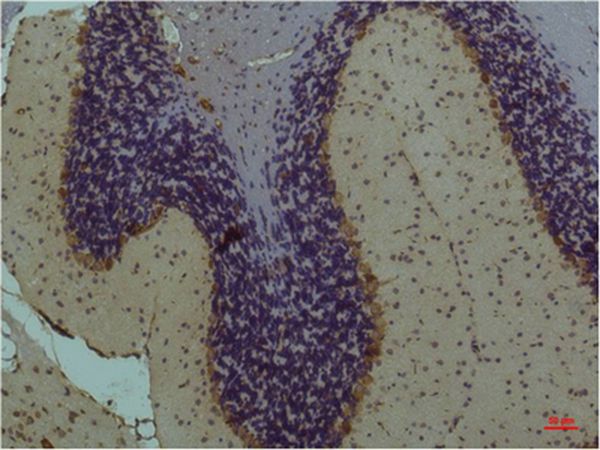

Immunohistochemical analysis of paraffin-embedded Mouse Brain Tissue using STAT3Mouse mAb diluted at 1:200.